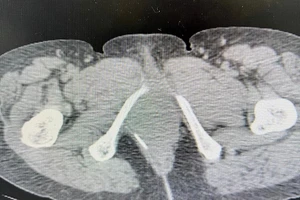

Cứu sống một nữ bệnh nhân nuốt tăm xỉa răng thủng trực tràng

Tăm xỉa răng lọt vào bụng đâm thủng ruột non